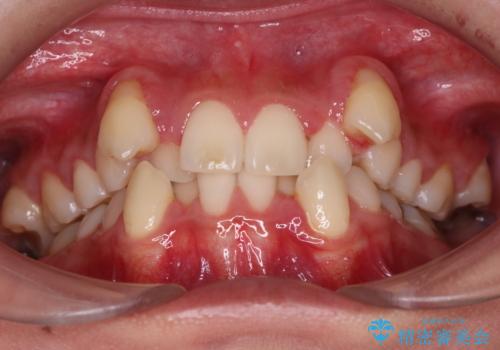

- 八重歯を主訴に来院された患者様です。

インビザラインによる矯正を希望され、今回は移動距離が少なくなるように犬歯を抜歯する治療計画としました。

抜歯矯正において、通常では4番(第一小臼歯)が抜歯の対象となることが多いのですが、今回は3番(犬歯)の歯肉退縮や装置の特性を考慮した治療計画となります。